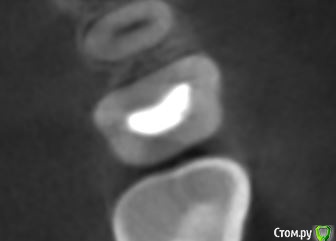

dmitrib81 Опубликовано 20 февраля, 2020 Автор Поделиться Опубликовано 20 февраля, 2020 еще фото Ссылка на комментарий